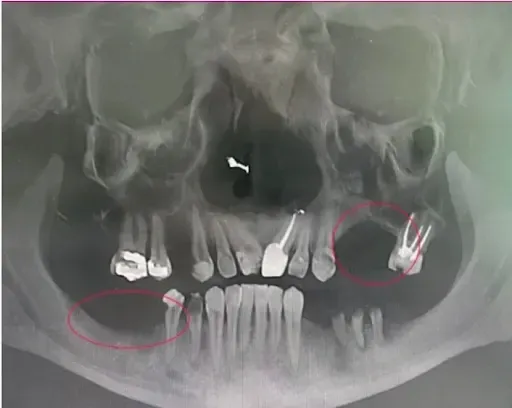

Zdjęcie CBCT/tomografii szczęki z widocznymi ciemnymi obszarami infekcji w kości

Infekcja w kości szczęki

Drugi skan tomografii z dramatyczną różnicą - osoba, która zwlekała za długo

Powyższe zdjęcie pokazuje zaawansowaną infekcję (ciemne obszary tam, gdzie powinna być zdrowa kość). Ta osoba zwlekała zbyt długo i nie kwalifikuje się już do implantów - skazana jest na tradycyjną protezę do końca życia.